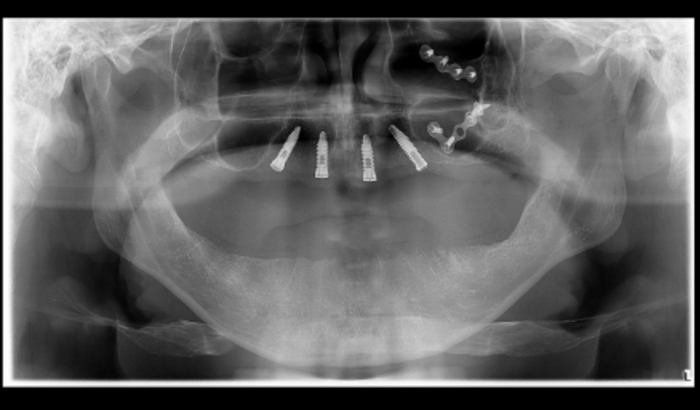

Meu nome é Alex Martins Pereira sou de Minas Gerais e atualmente moro no interior de Santa Catarina e criei essa vakinha porque preciso arrecadar a quantia de R$ 19.552,90 para fazer uma cirurgia pra retirada de pinos q estão com rejeição, causada por uma infecção e terminar de fazer meus implantes de protocolo devolvendo assim minha saúde bucal, capacidade de mastigação normal e principalmente meu sorriso.